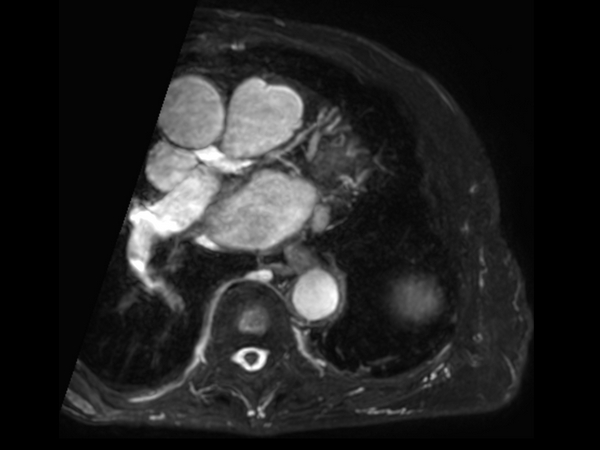

Acute myocardial infarction

Coronaries - LAD